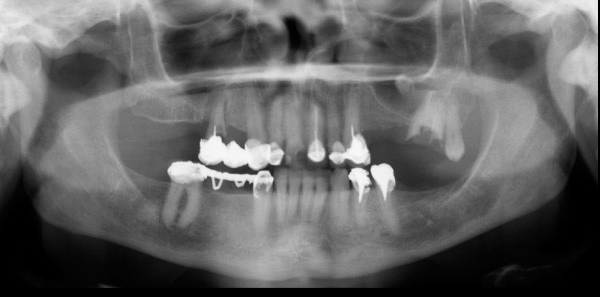

Paciente masculino 57años de edad, acude a la consulta para evaluación tomográfica previa a la colocación de implantes. En la radiografía panorámica observamos una imagen radiopaca proyectada en el antro del seno maxilar izquierdo. Se realiza estudio con tomografía volumétrica (Picasso E-WOO), se grafican cortes panorámicos, axiales, coronales y transaxiales que muestran claramente la imagen de densidad cálcica en el interior del seno maxilar izquierdo compatible con Antrolito.